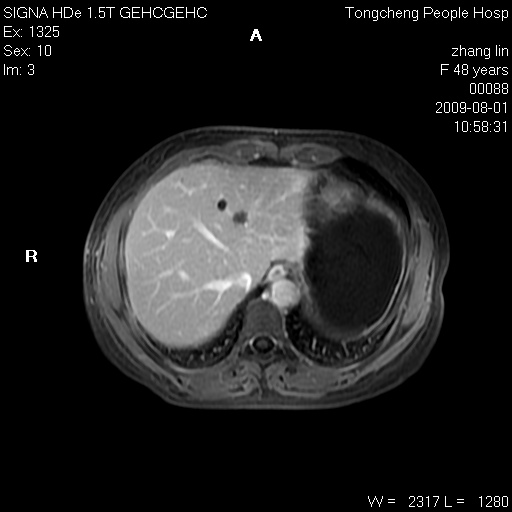

女,48岁。健康体检,彩超发现右肾占位性病变。平素健康。

临床诊断:右肾占位性病变,性质待定(囊肿?肿瘤?)。

上中腹部mr平扫+增强扫描,图像如下:

右肾上极见一类圆形病灶,t1wi呈等信号t2wi呈等高混杂信号,三期增强无强化,边界清---考虑囊肿出血。

同反相位均表现为等信号,病变无强化,考虑含蛋白的囊肿可能,弥散加权相或许有些帮助,